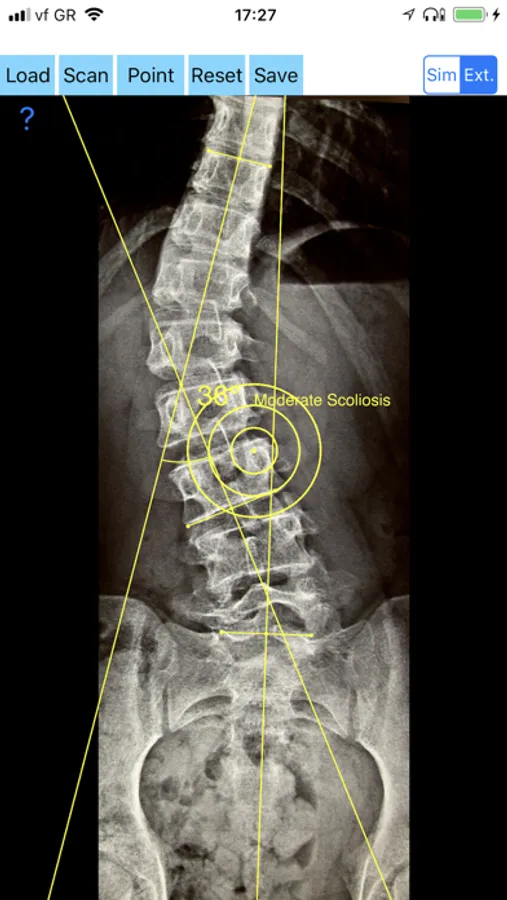

-Offers a very convenient way to determine the most accurate possibly way at once. By marking four points at the same X-ray, at each spine the App calculates the Cobb angle. In cases where values are out of normal ranges, the scoliosis is categorized according to measured angle as mild, moderate, severe. To simplify the process and to minimize inter-observer errors usually by not selecting the actual end vertebra, the app offers also in ext mode the ability to draw the vertical reference line through the patient’s sacrum and to identify more easily the end vertebrae s (ext method).

CobbAngleApp Screenshots